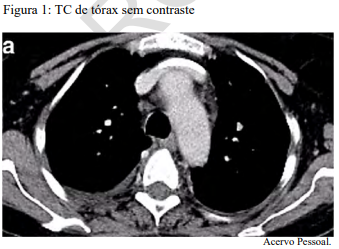

Um paciente de 62 anos de idade, tabagista ativo, cerca de 180 anos-maço, queixa-se de cansaço, tosse seca e perda de peso; por isso, procurou atendimento médico. O paciente referiu que pesava 100 kg e perdeu 10 kg. Realizou-se tomografia computadorizada de tórax, com evidência de lesão sólida de 2,1 cm em topografia de lobo inferior à direita, sólida, espiculada, com margens bem definidas e densidade de partes moles, assim como linfonodomegalia paratraqueal direita de 1,5 cm, paratraqueal esquerda de 1,2 cm e subcarinal de 2 cm. O paciente foi submetido a PET-CT de corpo inteiro, com evidência de hipercaptação de radiofármaco pela lesão (SUV 12) e eplo linfonodo representado na figura 2 a seguir.